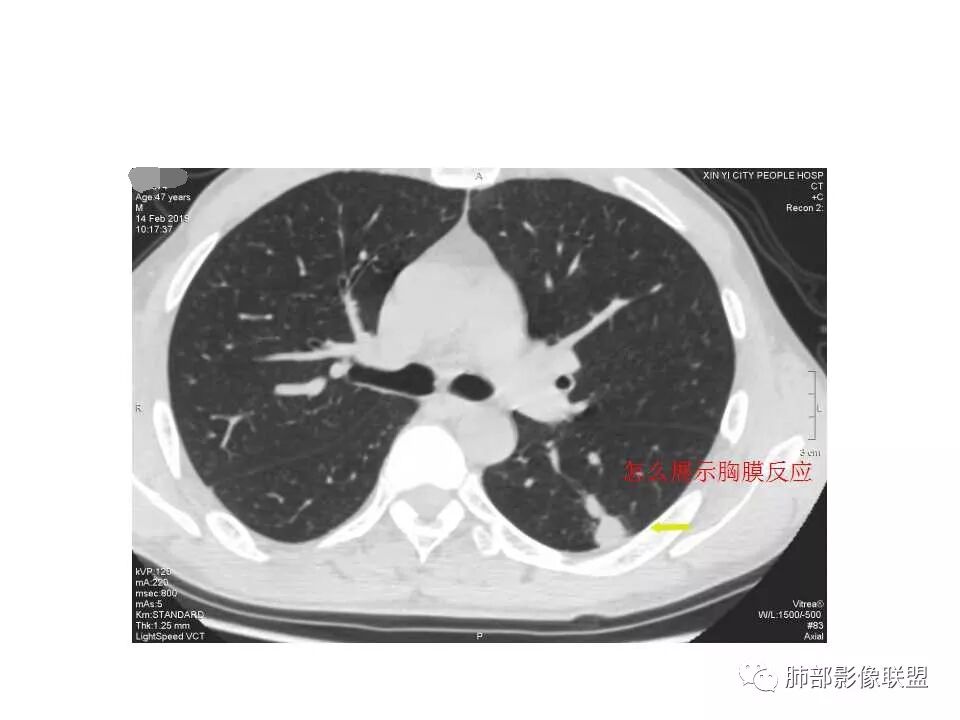

岁月:

我会做一做支气管的CPR,肺动脉的CPR。

因为南边的考虑一定要看到支气管,怎么办呢?

我很早以前做早癌,就是用CPR技术来观看病灶与支气管、血管的关系。

wonderful:

薄层

我的重建图像大部分是这样。

360旋转,可以观看意想不到的效果,我一直很重视这两种重建方法。比想象好 直观。